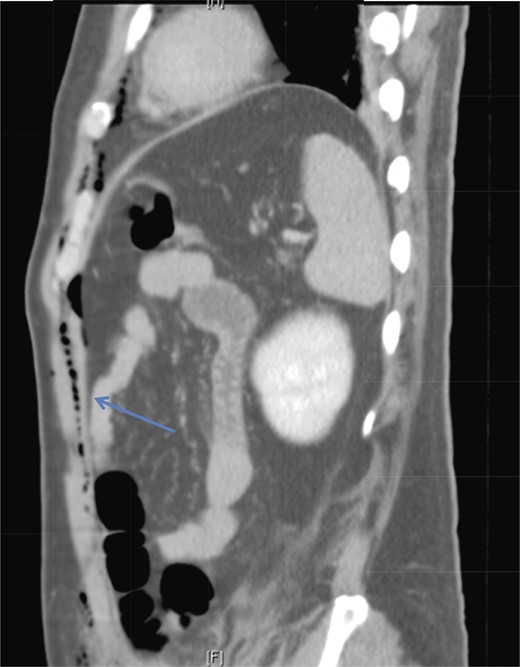

A 42-year-old male with a past medical history of hypertension was admitted for an elective TEP repair of his left inguinal hernia. Endotracheal intubation and general anesthesia were given uneventfully. The extraperitoneal space was developed with a balloon space maker, and insufflation of carbon dioxide at a maximum pressure of 12 mmHg was performed. Intraoperatively, a large incarcerated indirect left inguinal hernia containing omentum was reduced. A Optilene mesh (10 × 12 cm) was placed and tacked appropriately after hernia reduction. There were no obvious tears in the peritoneum and the total operative time was ∼90 min. No elevation of end-tidal CO2 was noted during the surgery and the patient was extubated successfully. The patient subsequently complained of left-sided chest pain on the same night of the surgery. He did not have abdominal pain. He had subcutaneous crepitus extending from the left groin to the left chest. His cardiac enzymes were negative and his electrocardiography revealed a sinus rhythm with no acute ischemic changes. A plain radiograph of the chest showed a sliver of lucency in the mediastinum suspicious for pneumomediastinum, with no obvious pneumoperitoneum or pneumothorax seen (Fig. 1). Computed tomographic (CT) imaging of the thorax and abdomen confirmed the radiograph finding of pneumomediastinum and diffuse subcutaneous emphysema tracking along the abdominal muscles bilaterally, as well as a small amount of free air and stranding in the left posterior pararenal space (Figs 2–4). The patient was treated conservatively with oral analgesia and supplemental oxygen. His chest pain resolved by the third postoperative day and he was discharged well. He was advised to avoid air travel for 1 month. He was reviewed in clinic at the 1-week and 1-month intervals and did not report any further chest pain or respiratory symptoms. His operation site healed well and he remained recurrence free.

Sagittal section of CT abdomen demonstrates air tracking along the anterior extraperitoneal space (arrowhead) into the anterior mediastinum and preperitoneal fat.